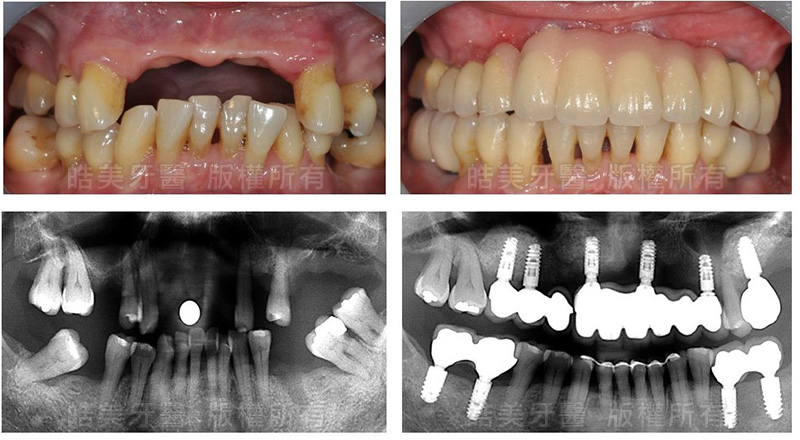

歯が歯がないので、林さんは十年間入歯を着用してきましたが、噛み合せの改善のため、インプラントを選びました。自家骨を移植して骨を再建しました。

詳細は写真のとおり